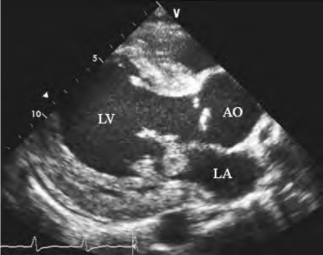

图13-20 二尖瓣赘生物二维超声图

左室长轴观示附着于二尖瓣前叶的絮状团块回声,边缘毛糙,收缩期脱入左房,为感染性心内膜炎赘生物声像图